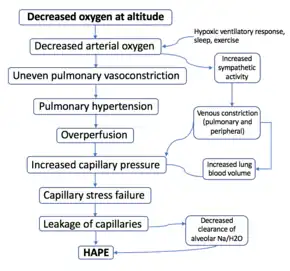

Though it remains a topic of intense investigation, multiple studies and reviews over the last several years have helped to elucidate the proposed mechanism of HAPE. The inciting factor of HAPE is the decrease in partial pressure of arterial oxygen caused by the lower air pressure at high altitudes (pulmonary gas pressures).[2][8][9] The resultant hypoxemia is then thought to precipitate the development of:

- Increased pulmonary arterial and capillary pressures (pulmonary hypertension) secondary to hypoxic pulmonary vasoconstriction.[8][10]

- Increased capillary pressure (hydrostatic pressure) with over-distention of the capillary beds and increased permeability of the vascular endothelium, also known as "stress failure."[8][11] This leads to subsequent leakage of cells and proteins into the alveoli, aka pulmonary edema.[8]

Hypoxic pulmonary vasoconstriction (HPV) occurs diffusely, leading to arterial vasoconstriction in all areas of the lung. This is evidenced by the appearance of "diffuse," "fluffy," and "patchy" infiltrates described on imaging studies of climbers with known HAPE.[8]

Although higher pulmonary arterial pressures are associated with the development of HAPE, the presence of pulmonary hypertension may not in itself be sufficient to explain the development of edema; severe pulmonary hypertension can exist in the absence of clinical HAPE in subjects at high altitude.[8][12]